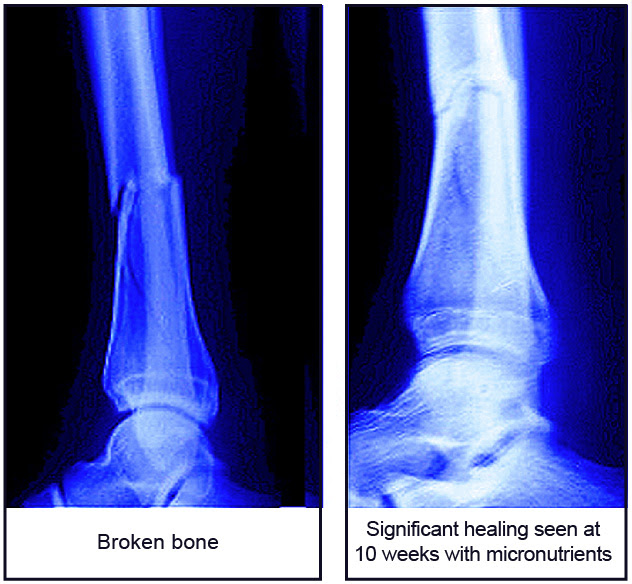

In a randomized double blind placebo-controlled clinical trial* involving 131 patients with tibial shaft fracture, we evaluated the effect of supplementation with collagen building micronutrients on the fracture healing time. The ages of study participants ranged from 15 to 75. We observed that the group of patients taking essential micronutrients containing vitamin C, lysine, proline, and vitamin B6 experienced faster fracture healing. Their fractures healed in 14 weeks, while it took 3 weeks longer for the patients taking the placebo (sugar pill) to experience similar healing. In addition, in about 25% of the patients in the supplemented group the bone fractures healed in as early as 10 weeks, while this was noted in only 14% of the patients in the control group. The patients in the supplemented group also reported improvements in a general feeling of well-being.

This study shows that a frequently missing factor in bone health – healthy collagen – plays an important role in optimum healing of bone fractures. A simple supplementation with specific micronutrients could greatly reduce healing time and patient suffering as well as lessen the economic burden on patient families and the healthcare system.